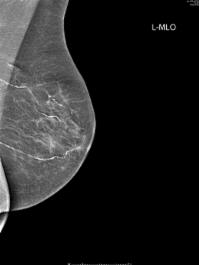

The Wessex Nuffield has dedicated breast imaging facilities including state of the art digital mammography. At the consultation you will have appropriate breast imaging (mammograms and/or ultrasound) performed and immediately reported by Consultant Radiologists with a special interest in breast radiology. If needed biopsies will be performed at the same time. We will be supported by suitably trained, dedicated mammographers, nurses and reception staff.